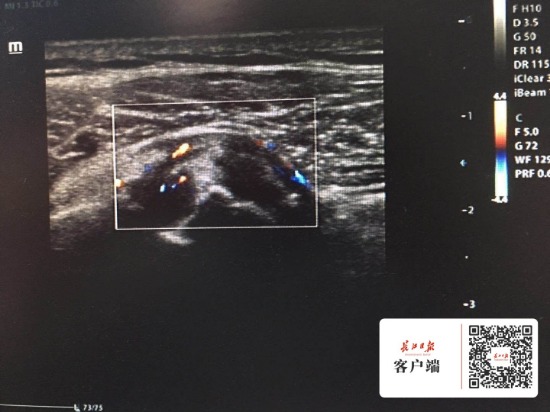

圖為超聲影像

接診的骨科醫生檢查后建議她做肩關節超聲檢查。超聲影像檢查時發現,劉女士的右肩無畸形、表面無紅腫,也沒有出現局部叩擊痛,主要是表現為活動受限,完成外展、上舉、后伸、內收動作均有一定困難,根據臨床癥狀結合相關超聲圖像,考慮為右側岡上肌局部全層撕裂伴周邊炎性改變,需要接受手術才能“治本”。